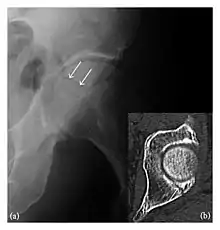

Figure 2: Posterior acetabular fracture in a 49-year-old woman presenting with hip pain after a fall. (a) Anteroposterior radiograph of the left hip shows a radiolucent line through the posterior acetabular wall (arrows). (b) Axial CT confirms the acetabular fracture (arrow).[1]